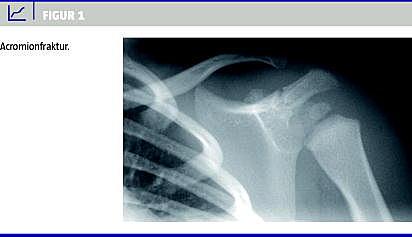

En 16 måneder gammel pige blev set på skadestuen på et regionssygehus, efter at hun to dage forinden havde haft et fald. Hun havde siden faldet ikke villet bruge sin venstre arm. På skadestuen blev der taget røntgenbilleder, der viste en acromionfraktur (Figur 1 ). Patienten blev sendt hjem, da frakturen skulle behandles konservativt. Da røntgenbillederne dagen efter blev gennemgået, blev der rejst mistanke om børnemishandling på grund af den noget usædvanlige fraktur. En søgning i EPJ blandt alle tilgængelige hospitaler gav resultat hos et centralsygehus, hvor patienten tre uger forinden var blevet undersøgt for columnafraktur. Patienten var angiveligt faldet to dage før iført et mariehønekostume, hvor hun var landet på en af dragtens vinger. Hun havde et stort hæmatom på ryggen, men der blev på daværende tidspunkt ikke fundet nogen frakturer, og hun blev sendt hjem. Ved denne undersøgelse fandt man normale forhold ved patientens skuldre og arme.

Summary The use of electronic medical records can contribute in diagnosing a case of battered child Ugeskr L&aelig;ger 2013;175(5):284-285 Child abuse is a very serious offence and is often underdiagnosed. This case report shows how the use of electronic medical records from different hospitals aided in diagnosing a case of battered child in a 16-month-old girl with an unusual acromion fracture. This illustrates the need for thorough investigation of the records in cases where a fracture might not raise suspicion on its own.